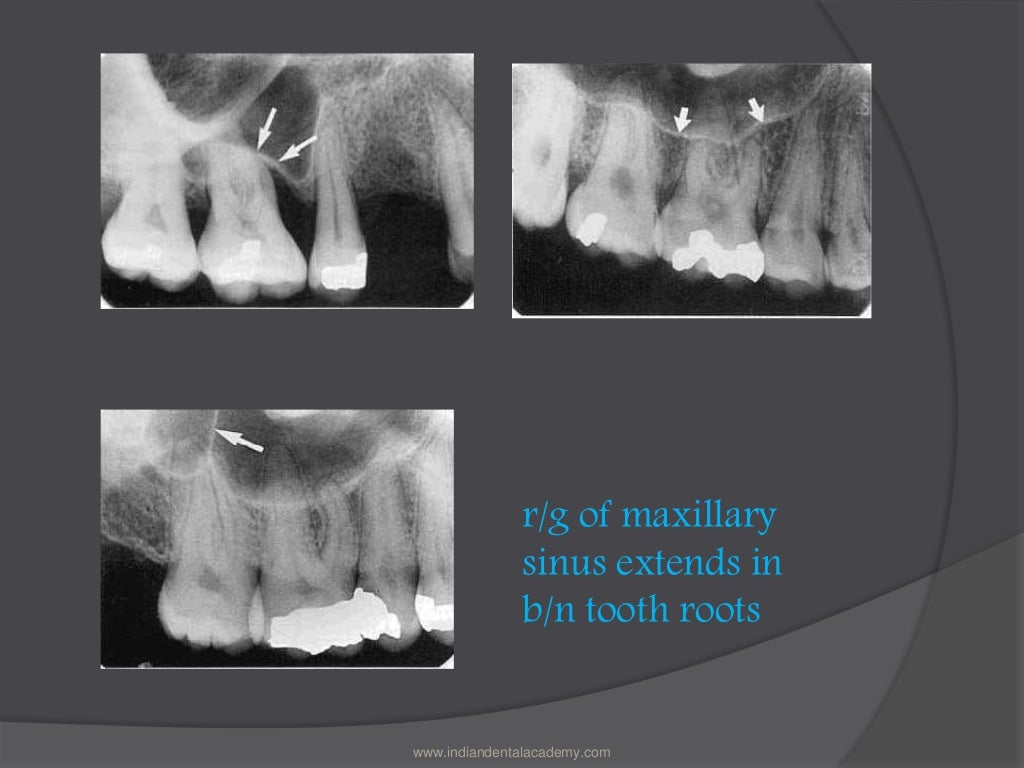

Define Radiolucency In Dentistry . Structures that are cavities, depressions, or openings in bone such as a sinus, fossa, canal or foramen will allow x. A radiolucency often represents a void or an area of tissue that. Identify various dental tissues and restorative materials on a radiograph. Explain, radiographically, why dental tissues and materials appear radiopaque or. The common opacities and lucencies are described. A periapical radiolucency is a hole in the bone formed as a result of inflammation under the root of the tooth as a means of housing the immune system to prevent the bacteria in the root canal from reaching the bone. This article discusses identification of radiopaque and radiolucent lesions noted on radiographs. It is a result of.